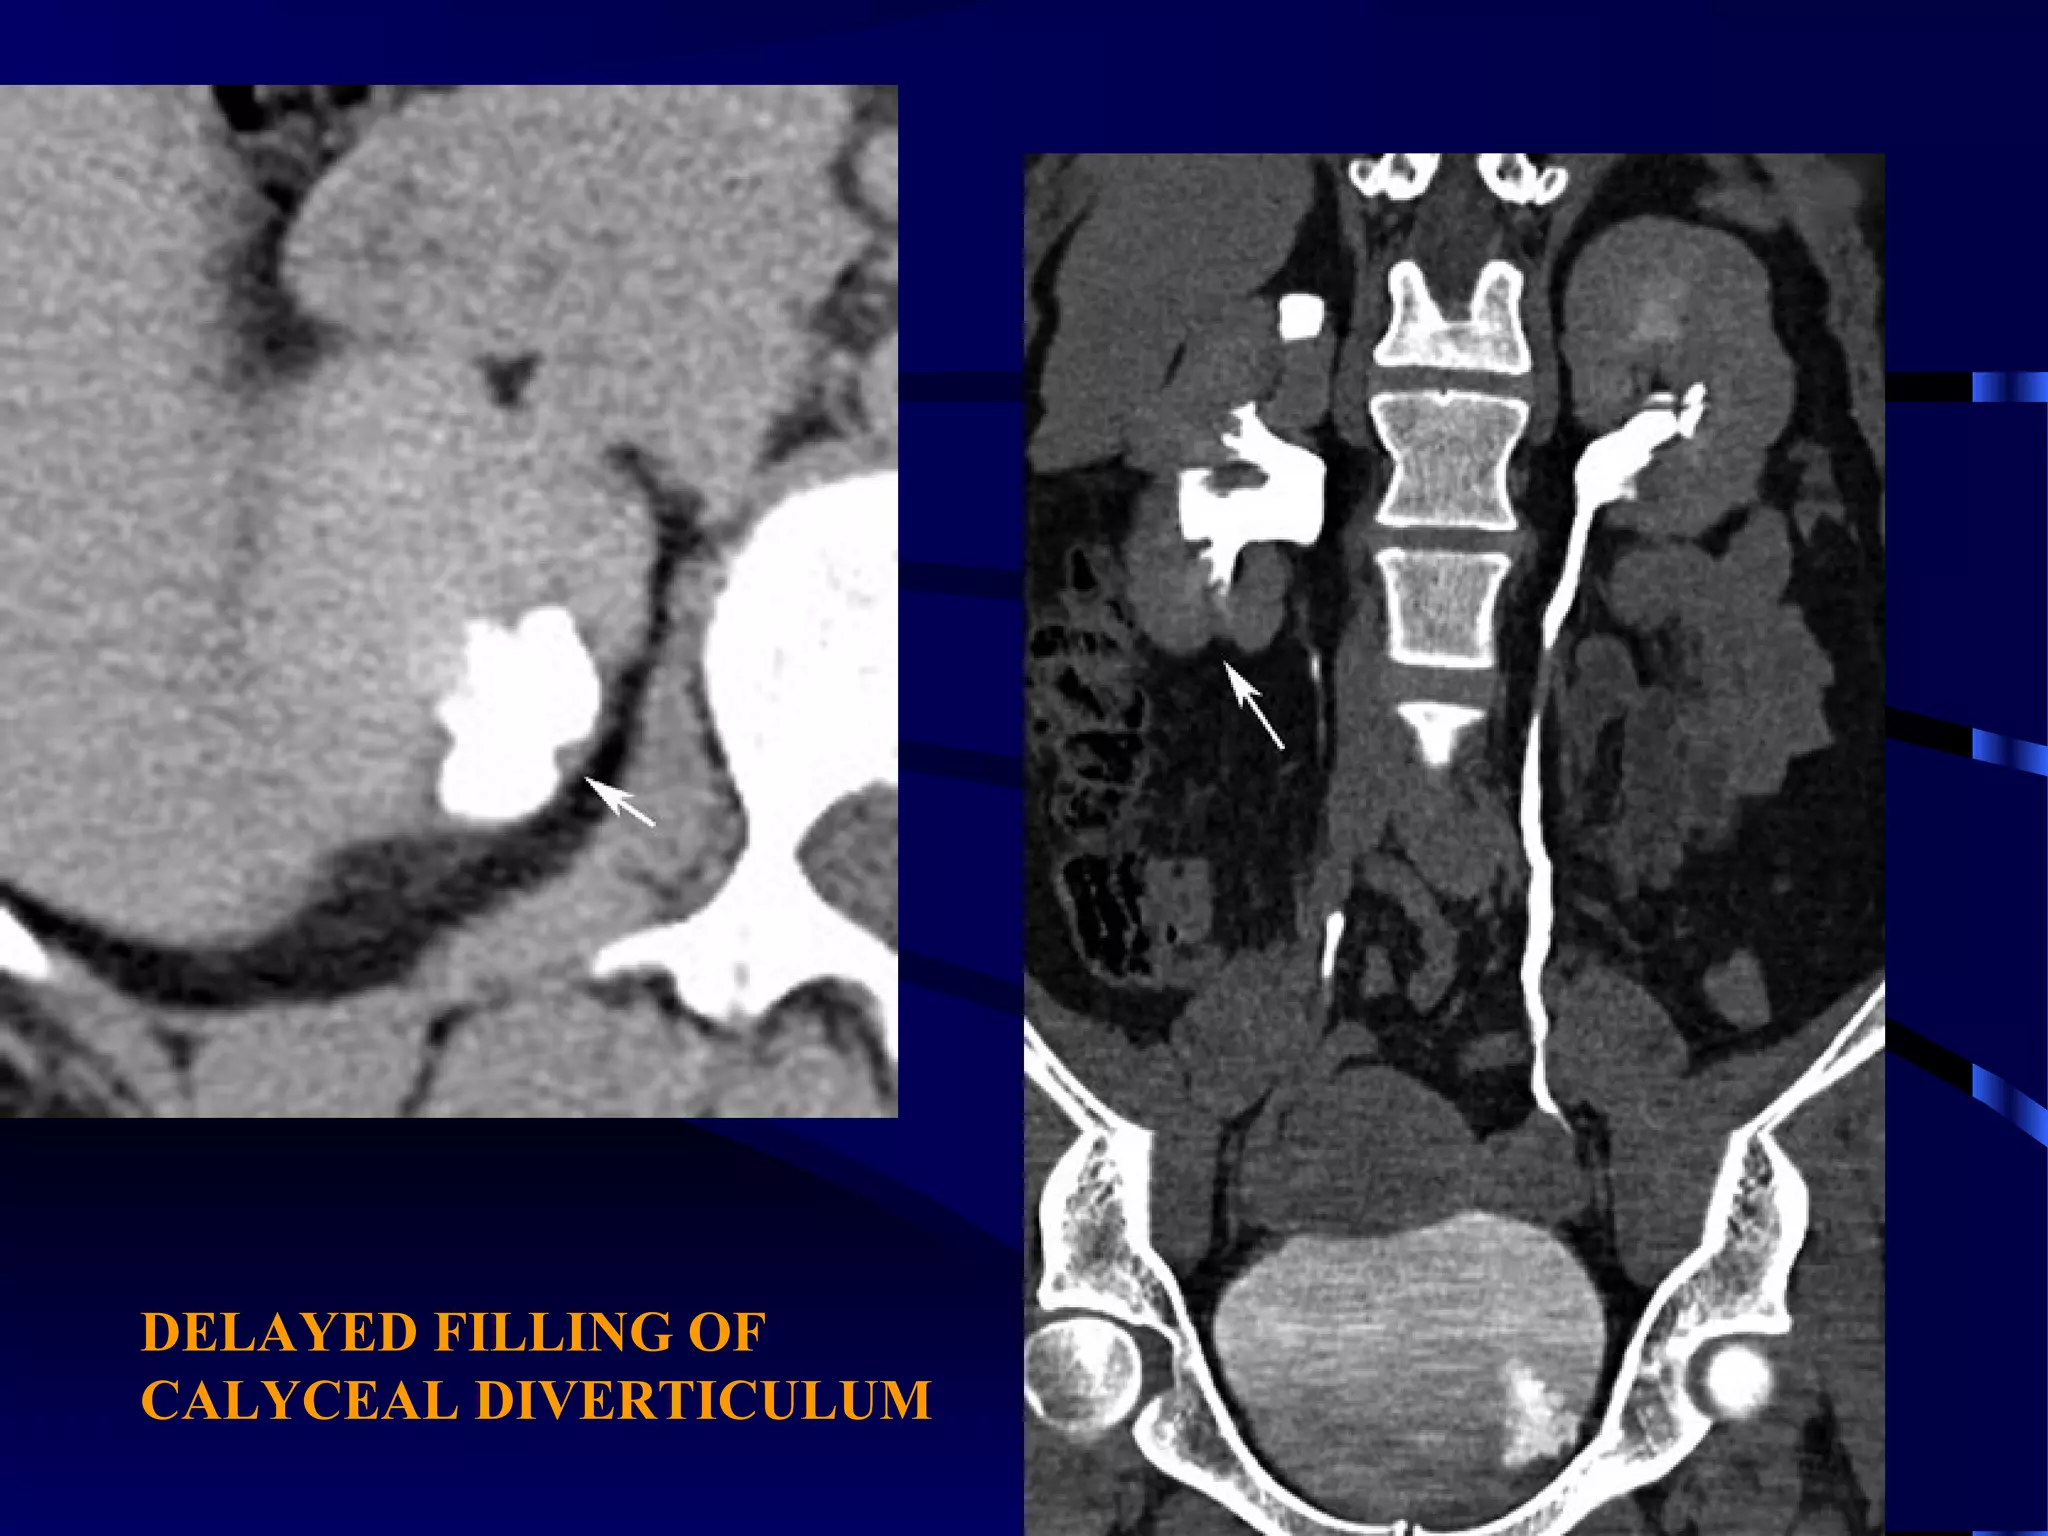

CASE (1)

NON ENHANCED CT ENHANCED CT

DELAYED FILLING OF

CALYCEAL DIVERTICULUM